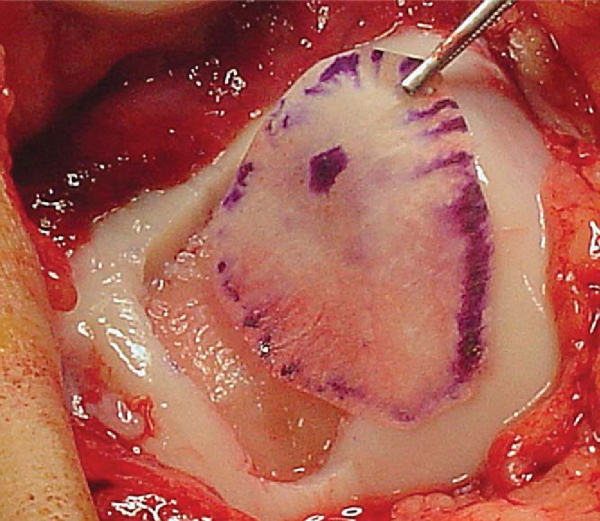

The periosteal graft is then aligned over the defect in the orientation matching the template, with the cambium layer facing the defect. The periosteum is then sutured to the cartilage rim with multiple 6-0 Vicryl interrupted sutures spaced every 2 to 3 mm (

Fig. 57-4

). If the defect is uncontained—meaning that there is not a circumferential rim of healthy cartilage through which sutures can be passed—suture anchors may be used to attach the periosteal graft on the uncontained side (

Fig. 57-5

). The knots should be tied on the periosteal side, not over the surface of the cartilage, thus minimizing any friction or toggling that could cause loosening of the knots. Redundant periosteal graft can be trimmed as the graft is being secured, ensuring that even tension is maintained on the graft. A small opening is maintained on one edge of the graft to allow injection of chondrocyte cells.